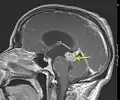

Low grade astrocytoma of the midbrain (lamina tecti), sagittal T1-weighted magnetic resonance imaging after contrast medium administration: The tumor is marked with an arrow. The CSF spaces in front of the tumor are expanded due to compression-induced hydrocephalus internus.